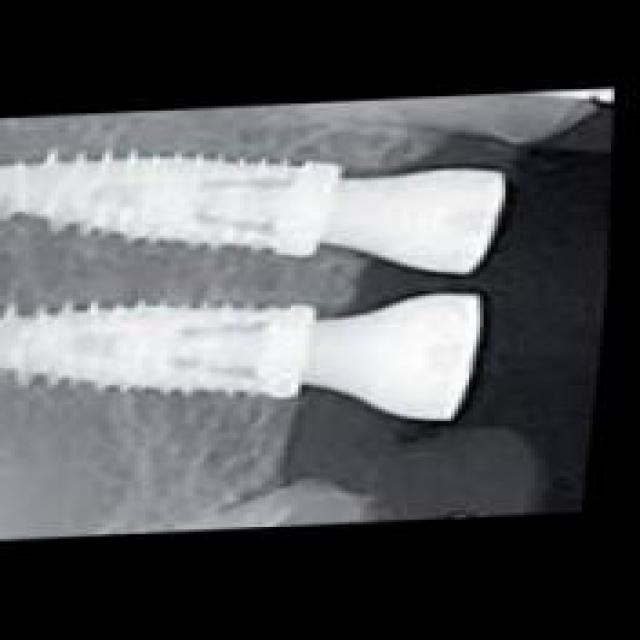

图片效果

在本研究中,我们采用了名为“rvg-v1”的数据集,以支持对牙片牙齿病变图像分割系统的训练,旨在改进YOLOv8-seg模型的性能。该数据集专门为牙科影像分析而设计,涵盖了多种常见的牙齿病变类型,具有重要的临床应用价值。数据集的类别数量为18,涵盖了从常见的牙齿病变到复杂的牙科情况,提供了丰富的样本以供深度学习模型进行训练和验证。

“rvg-v1”数据集中的类别包括:脓肿(Abscess)、磨损(Attrition)、骨丧失(Bone loss)、牙石(Calculus)、龋齿(Caries)、牙冠(Crown)、囊肿(Cyst)、填充物(Filling)、骨折线(Fracture line)、分叉(Furcation)、阻生牙(Impacted)、植体(Implant)、神经(Nerve)、根管治疗(Root canal treated)、根片(Root piece)、窦道(Sinus)、未萌出牙(Unerupted)以及一个通用类别(object)。这些类别不仅涵盖了牙齿常见的病变,还包括了一些较为复杂的牙科情况,能够帮助模型更全面地理解和识别牙科影像中的不同病变特征。